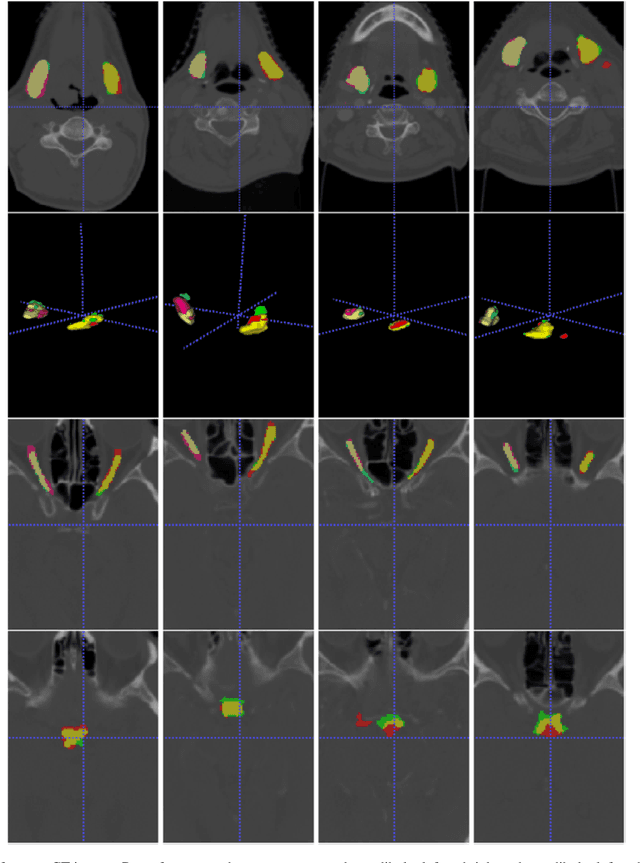

Abstract:Radiation therapy (RT) is a common treatment for head and neck (HaN) cancer where therapists are often required to manually delineate boundaries of the organs-at-risks (OARs). Automated head and neck anatomical segmentation provides a way to speed up and improve the reproducibility of radiation therapy planning. In this work, we propose the AnatomyNet, an end-to-end and atlas-free three dimensional squeeze-and-excitation U-Net (3D SE U-Net), for fast and fully automated whole-volume HaN anatomical segmentation. There are two main challenges for fully automated HaN OARs segmentation: 1) challenge in segmenting small anatomies (i.e., optic chiasm and optic nerves) occupying only a few slices, and 2) training model with inconsistent data annotations with missing ground truth for some anatomical structures because of different RT planning. We propose the AnatomyNet that has one down-sampling layer with the trade-off between GPU memory and feature representation capacity, and 3D SE residual blocks for effective feature learning to alleviate these challenges. Moreover, we design a hybrid loss function with the Dice loss and the focal loss. The Dice loss is a class level distribution loss that depends less on the number of voxels in the anatomy, and the focal loss is designed to deal with highly unbalanced segmentation. For missing annotations, we propose masked loss and weighted loss for accurate and balanced weights updating in the learning of the AnatomyNet. We collect 261 HaN CT images to train the AnatomyNet for segmenting nine anatomies. Compared to previous state-of-the-art methods for each anatomy from the MICCAI 2015 competition, the AnatomyNet increases Dice similarity coefficient (DSC) by 3.3% on average. The proposed AnatomyNet takes only 0.12 seconds on average to segment a whole-volume HaN CT image of an average dimension of 178x302x225.